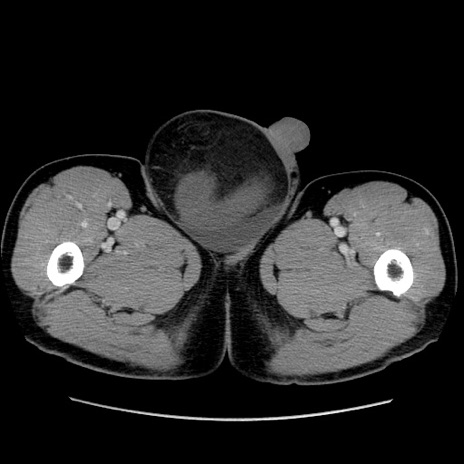

【症例】60歳代 男性

【主訴】右鼠径部膨隆

【現病歴】1年程前より右鼠径部膨隆あり。自己にて還納可能だったため放置していた。3時間前より右鼠径部の脱出を認め、還納困難となり受診。

【既往歴】高血圧

【身体所見】右鼠径部に小児頭大の膨隆あり。弾性硬であり、用手還納は困難。左鼠径部にも膨隆を認める。脱出はなし。

【データ】WBC 15500、CRP 測定なし